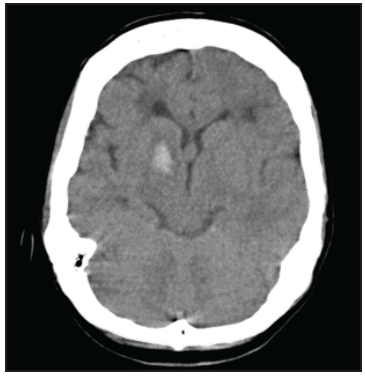

A 45-year-old female, ethnically mestizo patient with no significant past medical history was admitted to the emergency room of a quaternary hospital in the city of Cartagena (Bolívar) on July 1, 2019, due to a one week history of moderately intense holocranial headaches and a subsequent generalized tonic-clonic seizure, with sphincter relaxation and an unspecified length of the seizure. On admission to the emergency room, her blood pressure was 140/90 and the rest of her vital signs were normal with no focal neurological deficits. A simple computerized tomography (CT) of the head showed intraparenchymal hemorrhage in the right basal ganglia, mild multifocal small vessel ischemic disease, malacic changes in the right occipital region and an old left frontal ischemic event adjacent to the left lateral ventricle (Figure 1). The initial lab exams showed no abnormalities, with normal red and white blood cell and platelet counts, and nitrogen compounds, electrolytes and coagulation times all within normal limits. Cerebral panangiography found thinning of the internal carotid and posterior cerebral arteries (the latter seen in 50% of cases) with abnormal neovascularization in the basal nuclei, compatible with moyamoya disease (Figure 2). With these results, her possible treatment plan was assessed by a neurosurgery medical panel, concluding that she could benefit from endovascular treatment. However, in light of the high risk of recurrent bleeding, this procedure was postponed for at least four weeks.

In our case, moyamoya disease presented as a first generalized seizure with subsequent recovery, without apparent motor or cognitive deficits, caused by an intraparenchymal hemorrhage in the right basal nuclei detected through a simple cranial CT. This finding matches the literature which mentions that intraparenchymal hemorrhage is more common than the intraventricular or subarachnoid forms in patients with this disease, and that the most common locations are the basal nuclei, the medial temporal lobe, and the thalamus 1,4.